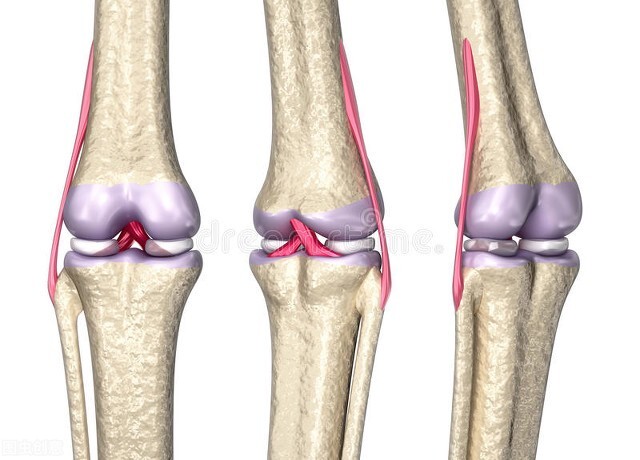

前交叉韧带是膝关节对抗向前移位的主要稳定装置。前交叉韧带撕裂是由膝关节的扭转或过伸*力暴**超过其强度所致。虽然可以出现部分撕裂,但是前叉韧带完全撕裂更常见。大部分前叉韧带撕裂为非接触性损伤。前交叉韧带损伤常伴严重的半月板撕裂、内侧副韧带的撕裂,少数情况下也会出现外侧韧带复合体或后交叉韧带的损伤。膝关节损伤造成的多发韧带损伤比较罕见,它们会导致严重的膝关节不稳,并且可以伴有腘动脉损伤;这是危及肢体的紧急情况。

可以通过查体及临床检查评估严重程度。应根据患者的年龄、活动水平需求以及是否合并其它损伤来制定前交叉韧带损伤的确定性治疗方案。对于年轻、活动量大的患者,前交叉韧带重建术可以最好的帮助他们恢复剧烈运动和减少半月板损伤。老年或者活动需求低的患者可通过物理治疗防止膝关节不稳。前交叉韧带功能支具对年老的和活动需求较低患者可能很有帮助,但对于大部分年轻的、期望恢复体育活动的患者,它不能提供足够的稳定性。采用重建手术具有高达90%的优良率。